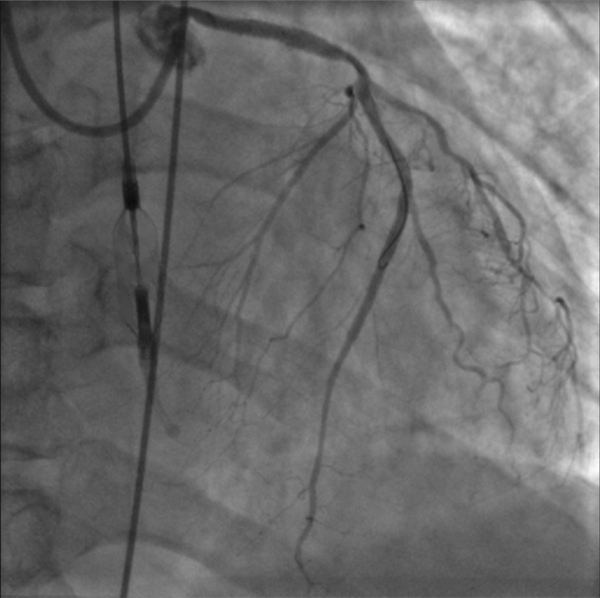

復(fù)查造影提示支架擴(kuò)張滿意,第一對角支殘余狹窄<30%,前降支中段至遠(yuǎn)段無殘余狹窄,TIMI血流3級。手術(shù)過程流暢,NyokAssist®操作便捷,過弓、跨瓣性能優(yōu)異,術(shù)中患者血壓平穩(wěn),心超顯示介入泵位置良好穩(wěn)定,主動脈瓣及二尖瓣未見反流加重。